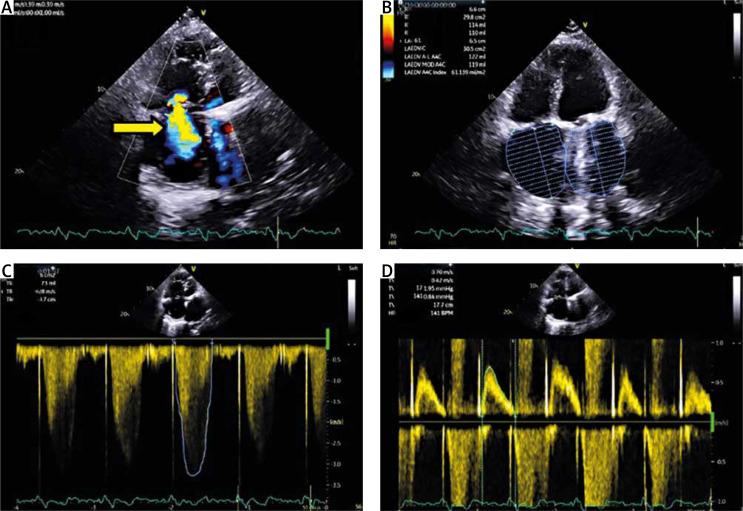

Hybrid procedure: mini-invasive tricuspid valve plasty with transvenous lead extraction.

https://cdn.ncbi.nlm.nih.gov/pmc/blobs/2924/11523476/34598f729f86/KITP-21-54881-g001.jpg